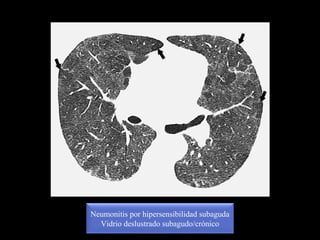

Neumonitis por hipersensibilidad subaguda

Nódulos centrolobulillares

Vidrio deslustrado subagudo/crónico